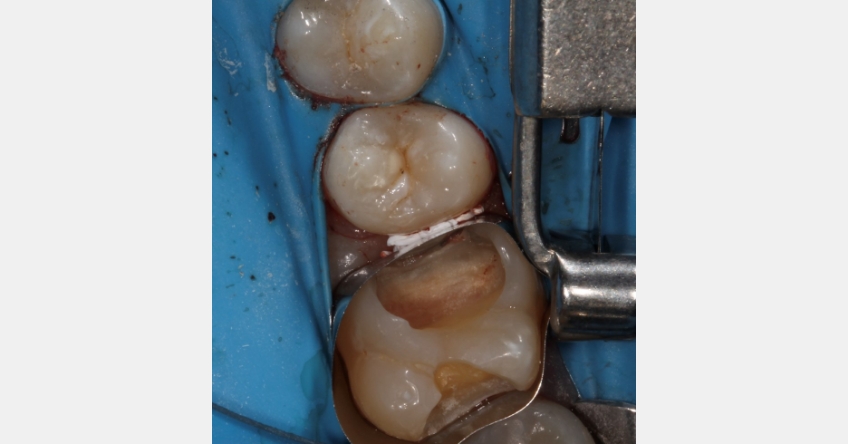

Use case #1: Deep margin elevation

Problem: It can be a challenge to achieve a precise margin when using restorative materials for deep margin elevation, because of the risk of material extruding into the gingival tissues.

Solution: The “matrix-in-a-matrix” technique is commonly used to seal the gap between the matrix band and the tooth. However, using Teflon tape is an alternative and equally effective approach. This technique, dubbed “the Belknap band” in honor of Dr. William Belknap, entails inserting a 2-inch strip of Teflon tape between the matrix band and the adjacent tooth, ensuring a snug seal that maintains the anatomical contour of the margin (Fig. 1). This method minimizes the likelihood of poor anatomical form or concavities.